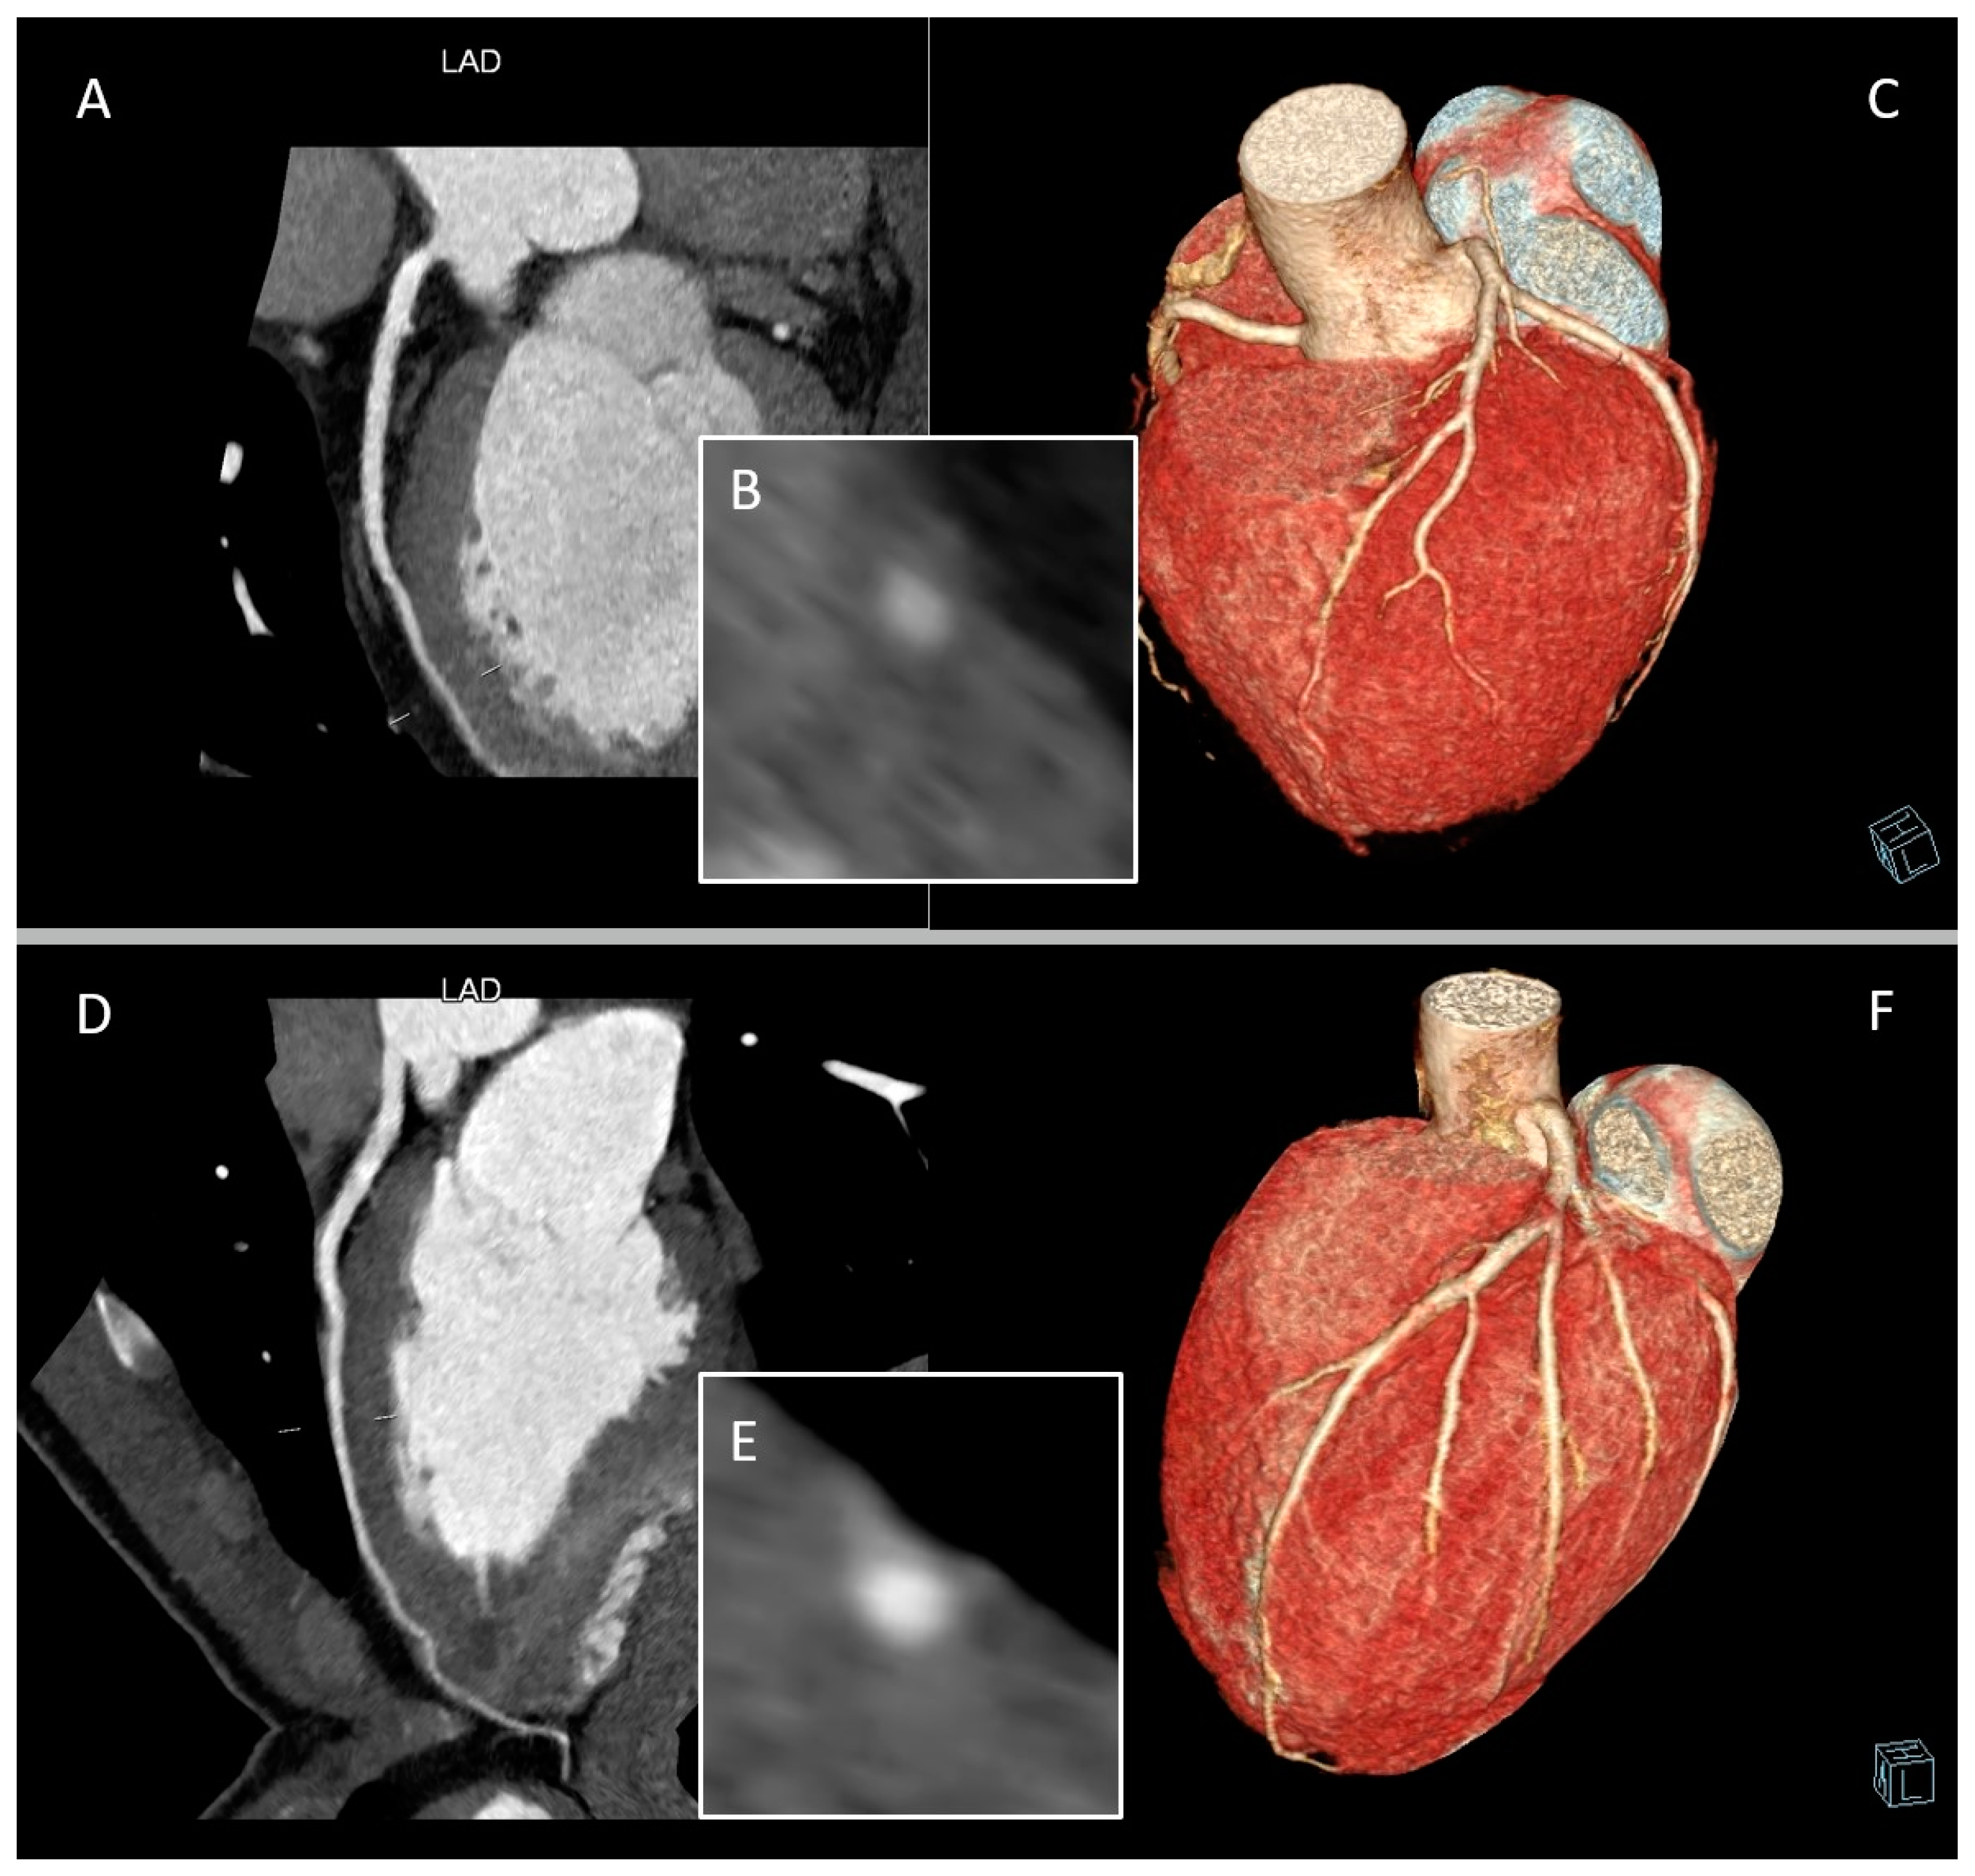

3. Role of CCTA: Anatomical Evaluation